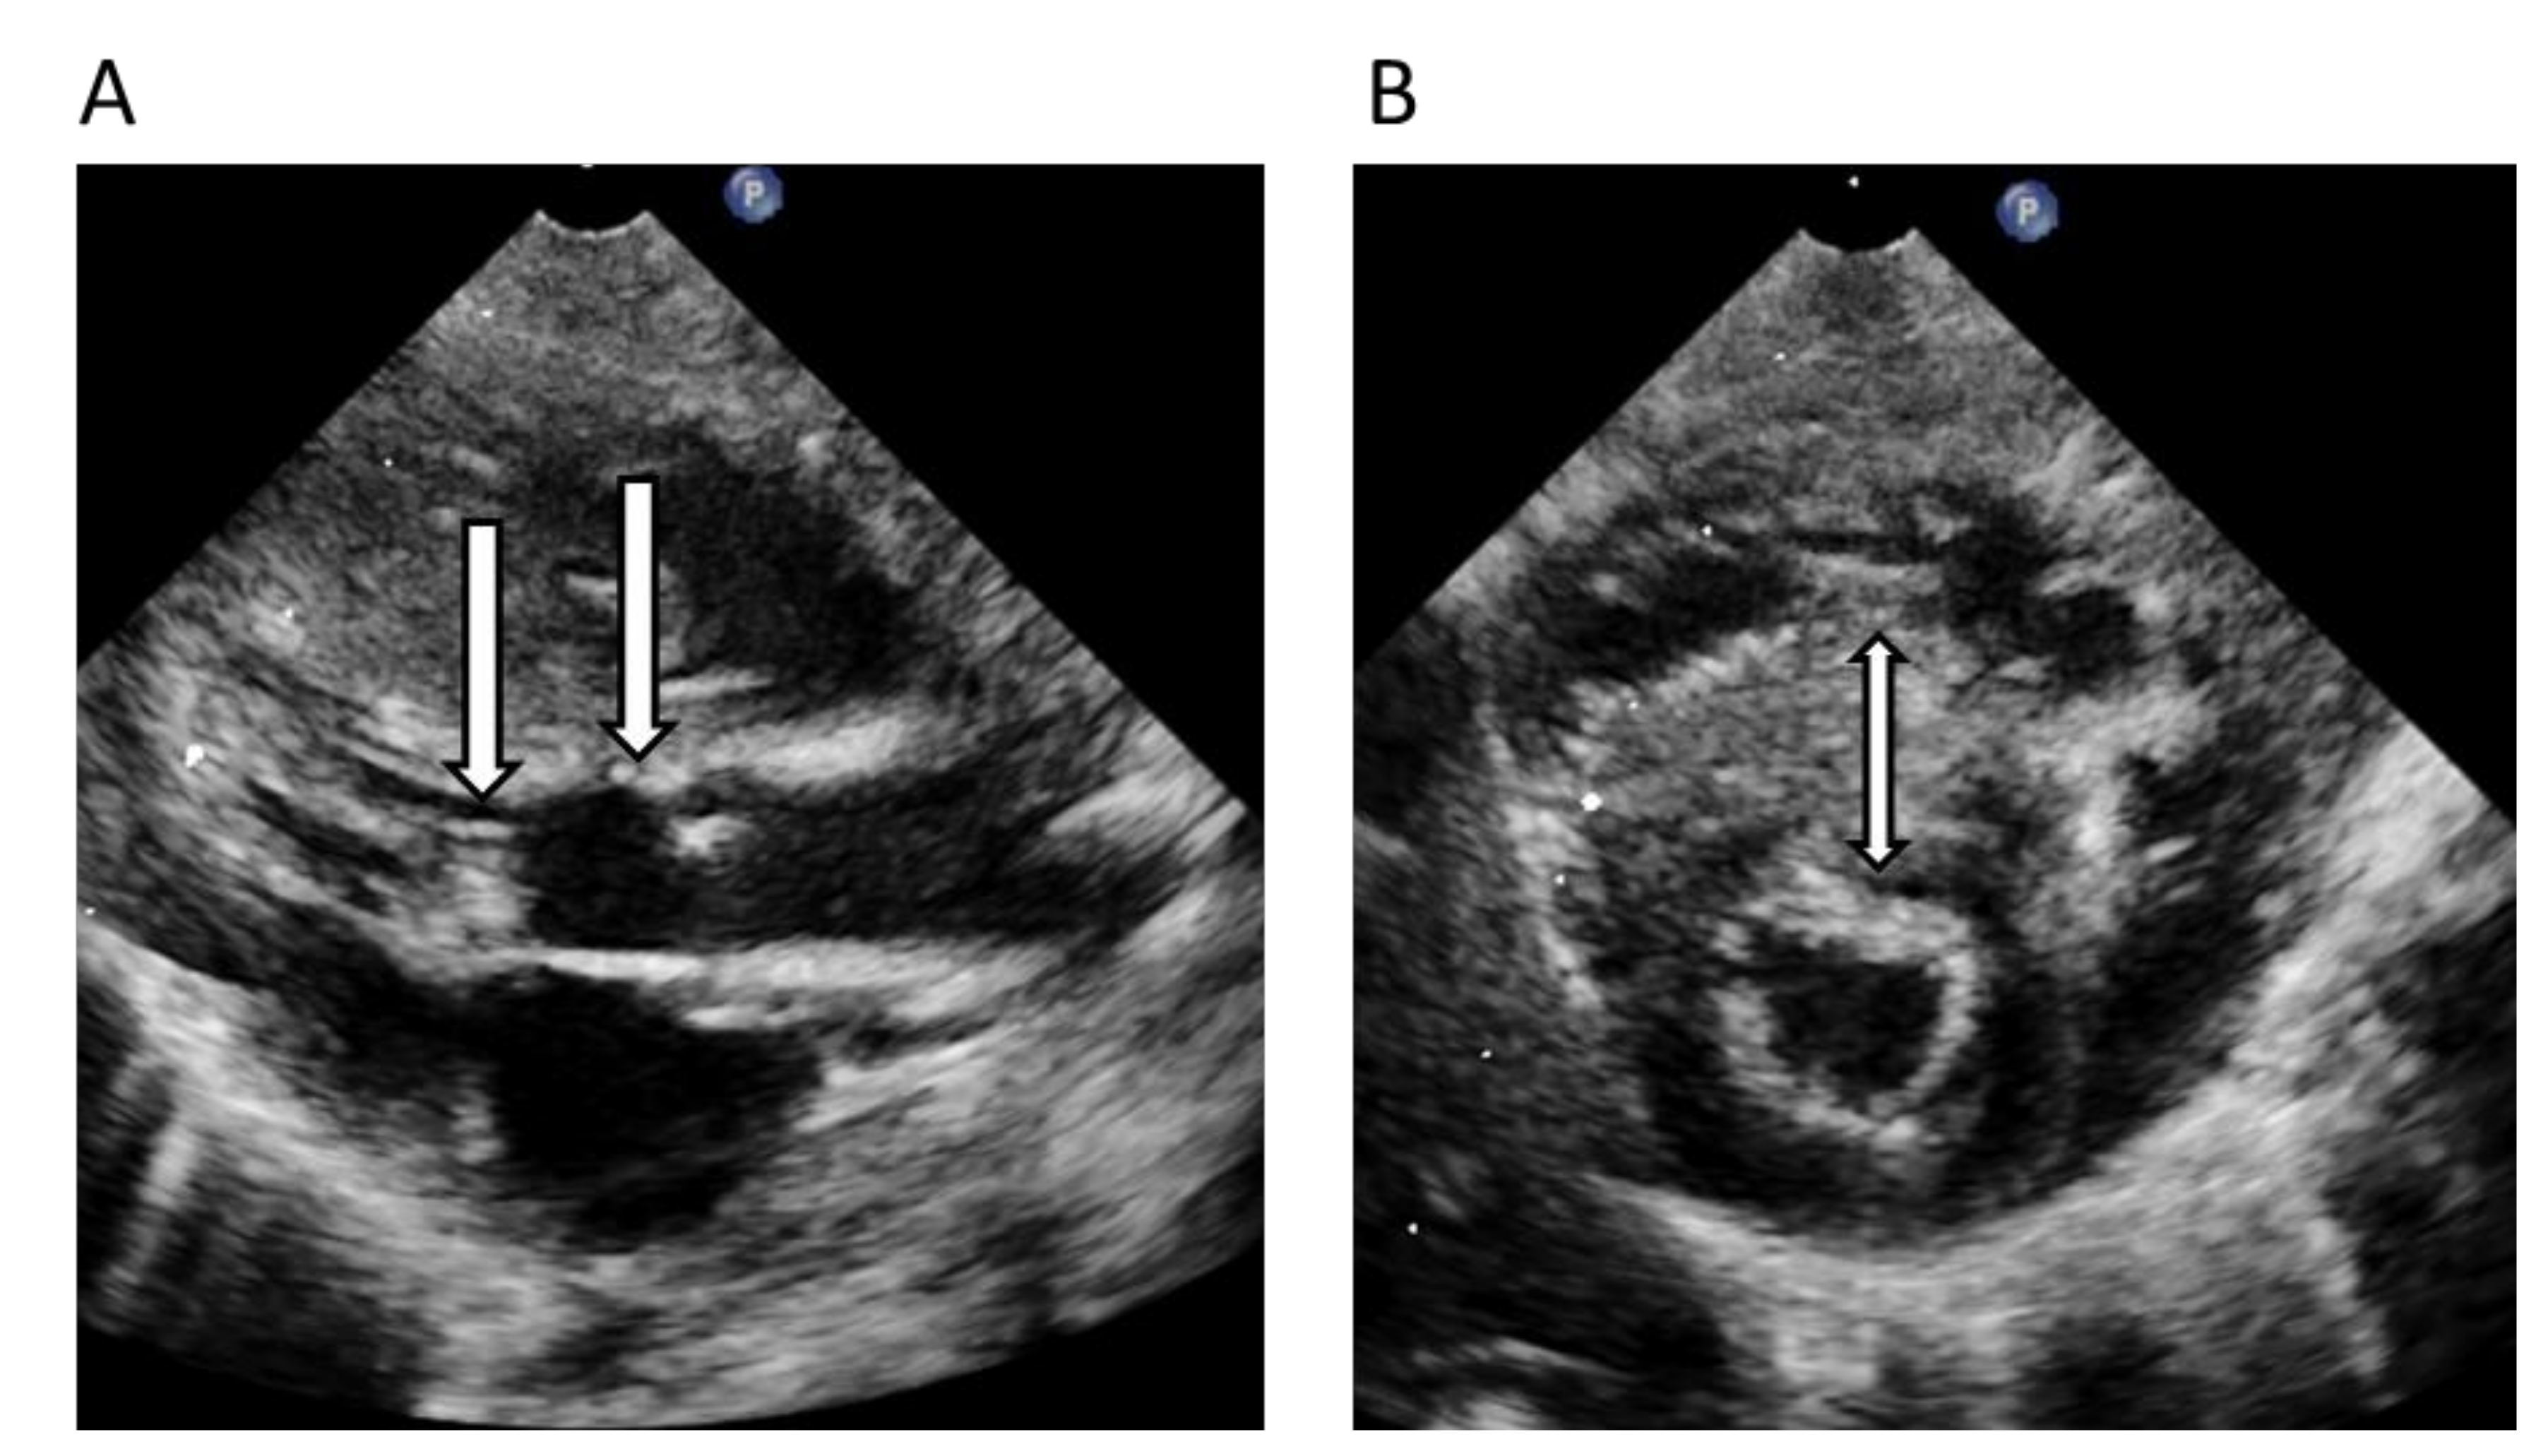

| 10. | IV:1 | 24 | M | 1 | ASH severe LVH | 3 | 7 | Mother with HCM, grandfather SCD and HCM, brother G+P- | ALPK3 Chr15(GRCh37):g.85370829del, NM_020778.4(ALPK3):c.903del, p.(Ile301Metfs*10) | PVS1 + PM2 Likely Pathogenic/Yes |

| Index | Variant | Protein | ClinVar | HGMD | gnomAD | SIFT/MT/PP * | CADD Score |